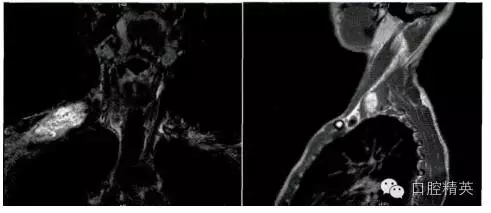

影像學(xué)檢查:頸部MRI(平掃+增強)提示右肩部鎖骨上區(qū)皮下軟組織內(nèi)一巨大腫物,大小約6.1 cm×2.8 cm,其內(nèi)信號不均勻,T1W1為等信號,T2W2為混雜高信號,考慮神經(jīng)源性腫瘤,右側(cè)臂叢神經(jīng)可疑受累(圖1)。臨床初步診斷為“右頸神經(jīng)鞘瘤”。

圖1.頸部MRI示右鎖骨上區(qū)皮下軟組織內(nèi)一巨大腫物